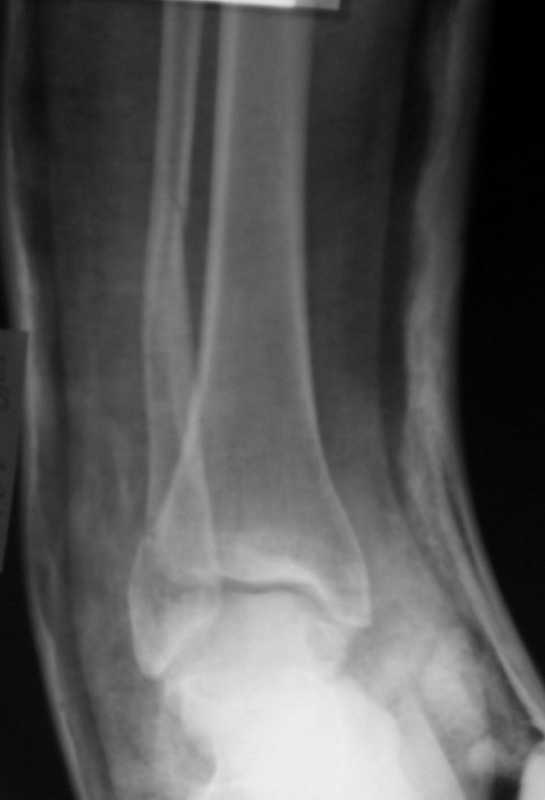

Перелом лодыжекКонтрольные рентгенограмы сделаны с нарушением укладок для стандартных проекций. Переделайте рентгенснимки и догда можно будет о чем-то иметь дискуcсию.

Рентгенограммы не сделаны в строго боковой и передне-задней проекциях.

Но и здесь видно, что внутренняя лодыжка "висит" - это говорит об интерпозиции. Выполняйте открытую репозицию и металлостеосинтез.

Можно сделать прямую с внутренней ротацией в 20 гр - еще лучше будет видно. Внутренняя лодыжка на боковом снимке не так уж плохо стоит. В любом случае - надо сделать нормальные снимки.

Вопрос к автору сообщения - эти лодыжки в задней гипсовой лонгете, судя по снимкам, или показалось?

Вот рентгенконтроль на 7-е сутки после репозиции.

Стандартными снимками считается прямая, боковая и мортиз!!!, а так трудно гадать, насколько потеря длины малоберцовой. На боковом снимке не сопоставленный перелом медиальной лодыжки и перелом заднего края без смещения.